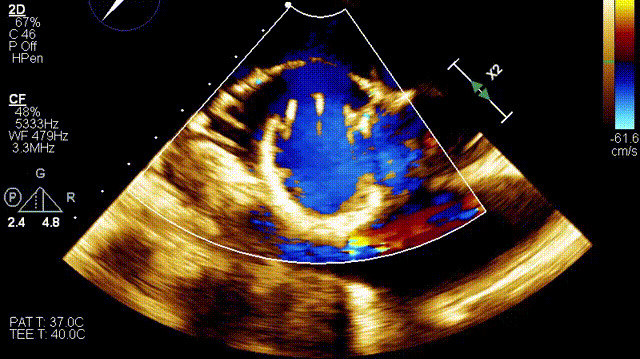

術(shù)后超聲

在這一研討會上,廈門大學(xué)心血管病醫(yī)院王焱教授帶領(lǐng)的結(jié)構(gòu)性心臟病團(tuán)隊,分享了應(yīng)用LuX-Valve Plus經(jīng)血管三尖瓣置換系統(tǒng),為一例超高齡三尖瓣重度反流患者開展經(jīng)血管三尖瓣置換手術(shù)。整個手術(shù)過程順利,術(shù)后患者三尖瓣反流顯著改善,標(biāo)志著LuX-Valve Plus經(jīng)血管三尖瓣置換系統(tǒng)在福建省的再一次成功實踐,為三尖瓣介入治療的醫(yī)學(xué)循證添磚加瓦。